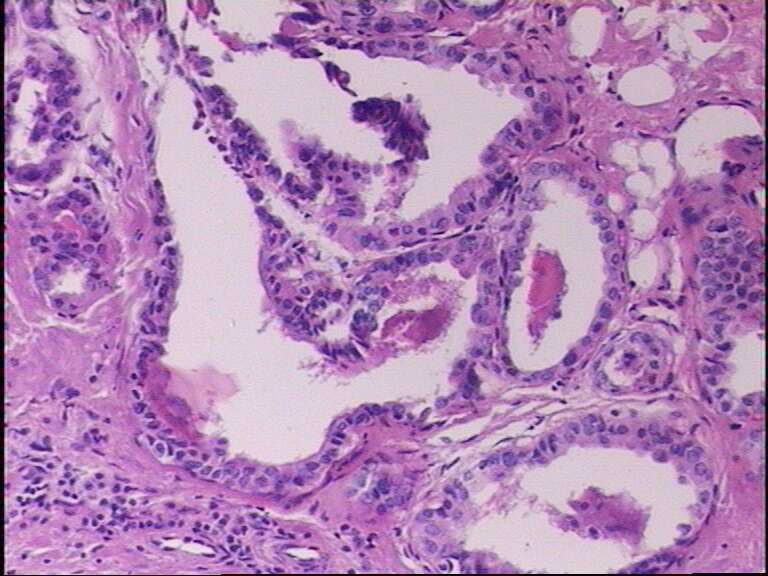

女43岁,甲状腺肿物

呵呵,大家看看够不够乳头状癌?图12-15再清晰些会更好。

嗯。图不好,不敢妄谈。但乳头相对比较宽大,细胞核大多圆形,可以排除经典型(common type)。

乳头状癌

就目前的切片看本例没有形成明确的以纤维结缔组织为轴心的乳头结构,前15张图更是连乳头状癌特有的核的表现(核拥挤、核沟、核内假包含体、毛玻璃核等)也不明显,而后传的7张图中核的改变都比前15张图中要明显,个人绝得诊断乳头状癌缺乏重要依据(1)明确的乳头结构(2)核拥挤、核沟、核内假包含体、毛玻璃核,所以希望重取材,多切片搜索可靠的诊断依据再下结论。

通过所给图片具备了乳头状结构,也有了核的一些特征,虽不典型:1、核椭圆形,2、核拥挤重叠,3、核上下分层,4、核沟等,可以诊断乳头状癌。